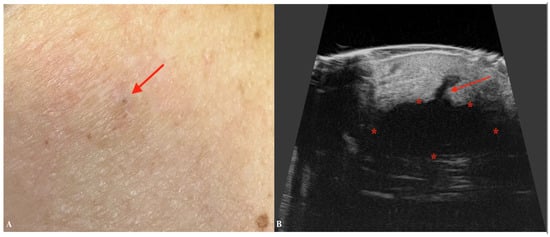

6. Mycosis Fungoides

| Mycosis Fungoides | Presence of a subepidermal low-echogenic band (SLEB). Useful in monitoring disease progression and response to therapy. |